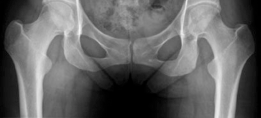

We review everything you need to understand about Open Hip Dislocation: How Fascia Lata Autograft Restores Stability. A 25-year-old female with left hip posterior femoroacetabular impingement received treatment via surgical hip dislocation. The procedure involved posterior wall rim trimming and labral reconstruction using a fascia lata autograft. This intervention successfully addressed chronic posterior hip pain and associated labral pathology stemming from a prominent posterior acetabular wall.

Standard preoperative imaging must include an anteroposterior (AP) pelvis, cross-table lateral, and false-profile view of the affected hip. These evaluate for dysplasia, impingement morphology (cam/pincer), and degenerative changes.

Closure and Osteotomy Fixation

Once the graft is secured, the hip is taken through a dynamic range of motion to confirm stability and assess for impingement. The native remnant capsule, if present, is imbricated over the graft. The trochanteric flip osteotomy is reduced and fixed using two or three 4.5 mm fully threaded cortical screws directed medially and slightly proximally toward the lesser trochanter. The fascia lata defect from the harvest site is partially closed if possible, avoiding compartment syndrome, and the remainder of the wound is closed in layers over a suction drain.